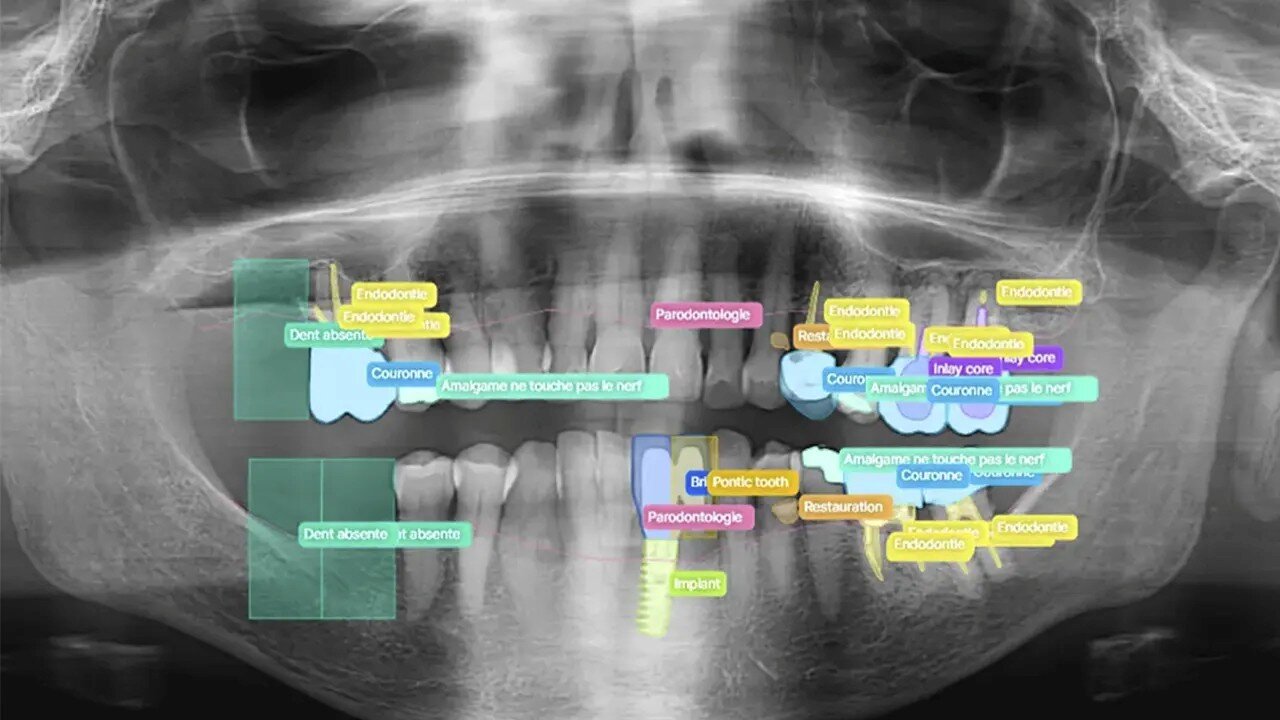

یکی از مهمترین کاربردهای هوش مصنوعی در حوزه دندانپزشکی، ارتقای دقت در فرآیندهای تشخیصی است. الگوریتمها با تحلیل تصاویر رادیوگرافی، اسکنهای سهبعدی و دیگر دادههای تصویری، قادرند ناهنجاریها و بیماریهایی مانند پوسیدگیهای اولیه، ترکهای مینا یا مشکلات پریودنتال را با دقتی بسیار بالاتر از چشم انسان تشخیص دهند.

طبیعتا! توانایی در تشخیص زودهنگام و دقیق، به متخصصان در سراسر جهان این امکان را میدهد که رویکردهای درمانی را به سمت کمترین تهاجم سوق دهند. برای مثال، اگر یک پوسیدگی در مراحل اولیه با دقت بالا تشخیص داده شود، متخصصان میتوانند از رویکردهای درمانی سادهتری مانند پر کردن دندان استفاده کنند؛ در حالی که در روشهای سنتی، ممکن است تنها در مراحل پیشرفتهتر به چشم آید و نیاز به درمانهای پیچیدهتر باشد. این تغییر رویکرد، در نهایت به حفظ حداکثری ساختار دندان طبیعی کمک میکند.